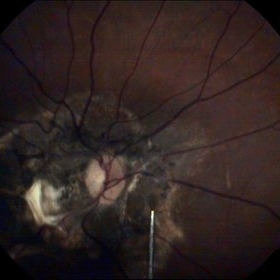

Myopic Degeneration

Sep 10 2014 by Mehul A Shah

Chorio retinal atrophy.

Photographer: Drashti Netralaya

Imaging device: Zeiss FF450

Condition/keywords: myopia